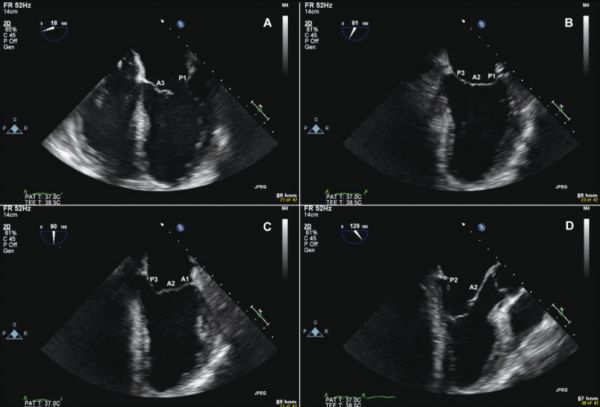

Tiến hành thăm dò mặt cắt từ mỏm được nhận xét là sẽ khó hơn nhưng kỹ thuật này có tác dụng trong so sánh kích thước buồng thất và là cửa sổ tốt nhất nhằm đánh giá những bất thường về vận động ở vùng vách liên thất và thành tim. Đây là hình ảnh mặt cắt 3 buồng tim từ mỏm trong siêu âm tim bẩm sinh. Mời các bạn tham khảo!

Trên đây là hình ảnh Mặt cắt 3 buồng tim từ mỏm, hy vọng sẽ hữu ích cho các bạn trong quá trình tìm hiểu và chẩn đoán bệnh!